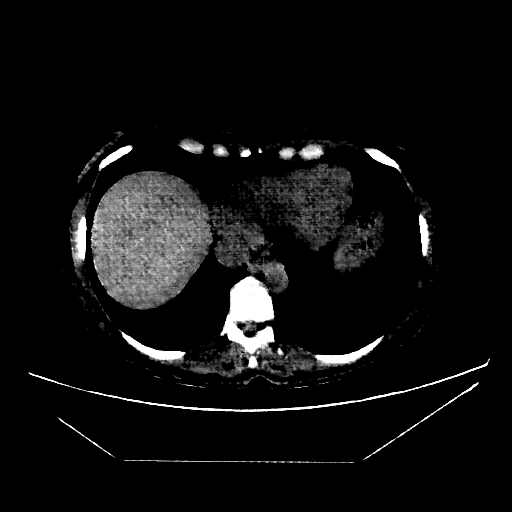

Original VENOUS CT scan

Full window (WL 1023.5, WW 4095 β†’ Low βˆ’1024, High +3071)

Lung window (WL -600, WW 1500 β†’ Low βˆ’1350, High +150)

Generated VENOUS CT scan (A→B translation)